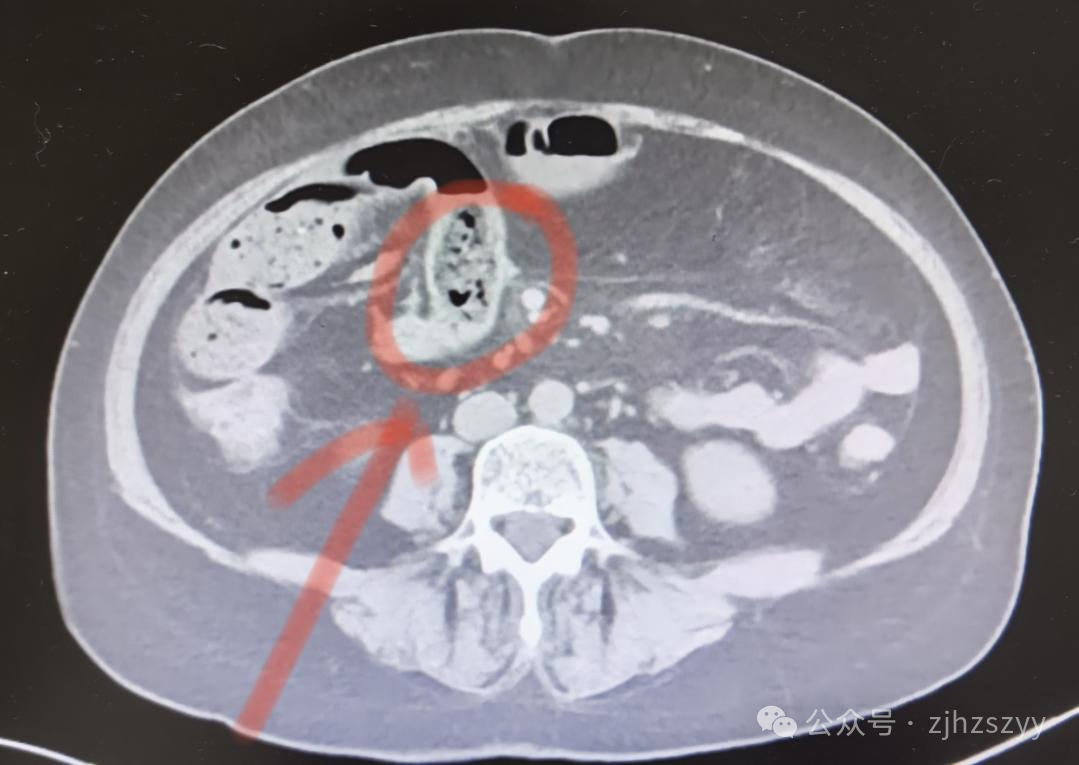

10月21日,浙江杭州58岁的宋女士一连吃了好几个柿子。没想到第二天,腹部就出现阵阵绞痛,难以忍受,到杭州市中医院检查确诊为小肠肠梗阻。在收治入院过程中,她的病情急转直下,还出现了腹腔积液。医院紧急安排手术,将一块比鸡蛋还大、坚硬如石的“柿石”取出,一周后患者顺利康复。

图源:杭州市中医院